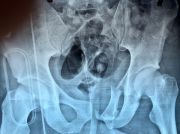

1. Pelvic fracture involved sacrum caused by lateral compression in a 25-year-old male.

Treatment: Percutaneous fixation with two sacroiliac screws

I. Before surgery, axial view of CT scan showing fracture of sacrum on the left side II. Post-surgery, anteroposterior x-ray of pelvis with the two sacroiliac screws